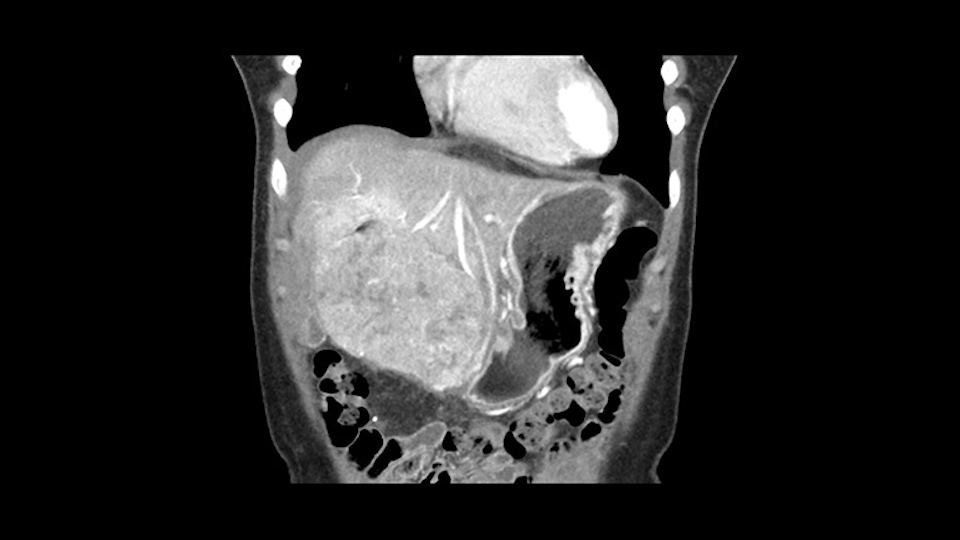

So if we look at the CT scan, on the axial, it’s a larger lesion. It’s about 6 or 7 or 8 centimeters. So it does look a bit threatening in terms of its resectability but if you really drill down deeply into the anatomy, and I think the coronal [imaging] is even better, you can see that the entire mass is on the patient’s left side of the falciform ligament. So it’s really only a left-sided tumor and not even really a left-sided tumor because Segment 4 is uninvolved anatomically.

As I review the CT scan, we have both arterial and venous phases, the tumor is obvious. But I’ll start by saying that the liver itself does not appear to be cirrhotic to my eye. It’s got a normal contour and allied to that, that I do not see evidence of portal hypertension. The spleen is normal, there’s no collateral vessels. The tumor itself, I measured maximally at about 11 centimetres in diameter and I’m told the alpha fetoprotein is very high (over 10000), which is entirely consistent with this being a solitary hepatocellular carcinoma that is very exophytic. It seems to emanate off the inferior margin of Segment 3 (because that’s the falciform). I’ll start by saying that this is not transplantable. The tumor exceeds our guidelines for transplantation, but it's likely resectable based on normal liver and no portal hypertension.

Hi my name is Sedat Karademir. I’m from Ankara Guven Hospital and I’m an HPB and transplant surgeon. We are discussing about the case I reviewed the CT of 41 year old lady with a suspected hepatoma in the left lateral segment. Presumably its Segment 3. It looks like a big tumor sitting exophytically mostly out of the liver and pressing on the surrounding organs, but it doesn’t look like any invasion there. In this situation, according to the venous and arterial anatomy, it looks like this will be a Segment 2 and 3 resection.

The other thing I would do in this case is to certainly to assess the coronal phase as we can see in the coronal phase, this tumor looks like it's growing from Segment 3, and again I don’t think there’s involvement of the right side of the liver or even on Segment 4.

La decisión aquí, y otra vez mirando, me parce importante mirar a los cortes coronarios porque parece que este tumor cuelga del segmento tres y aquí la cuestión va a ser si vamos a realizar una resección más limitada y hacer una recesión del segmento tres, o si vamos a tener que realizar una hepatectomia izquierda. En cuanto a puntos importantes en ambas opciones, en todos los casos vamos a intentar realizar un recesión anatómica ya que hay datos en la literatura que parecen indicar que una resección anatómica tiene mejores resultados oncológicos comparado con una recesión no anatómica; entonces realizaremos una resección del segmento tres y en este caso trataremos de buscar el pedículo que va al segmento tres, en este caso probablemente sea una resección del segmento tres, realizare una maniobra de Pringle y clampare el hilio para evitar el sangrado.